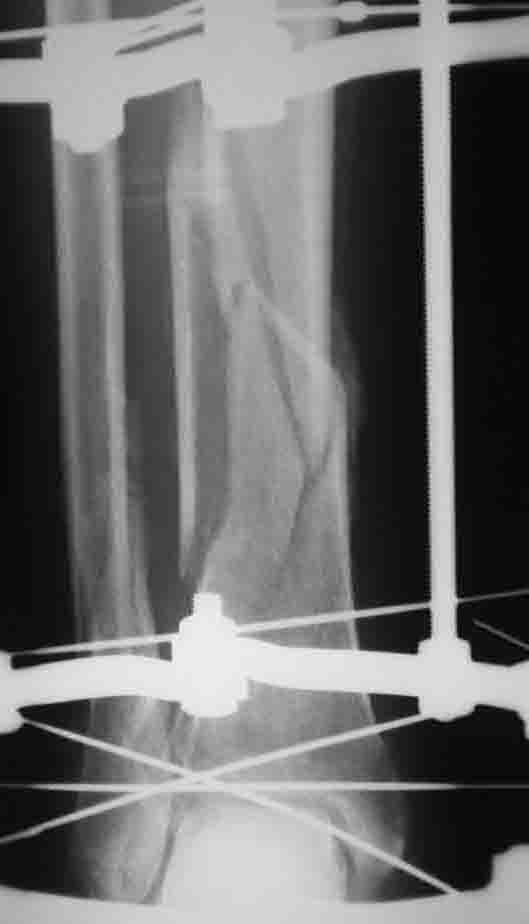

вот при таком внутрисуставном переломе ВЧКО по Илизарову будет методом выбора во многих (возможно, в большинстве) британских центров, где этой методой владеют.

Где не владеют - пусть накладывают опорные пластины. я не против :)